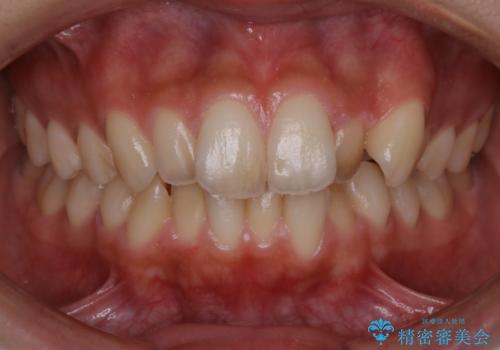

前歯のデコボコした歯並びをマウスピースで改善!

- 前歯の歯並びの改善を希望され来院された患者様です。

矯正装置としてはマウスピースを使用しています。

見た目、嚙み合わせ及び、治療期間や施術内容に大変ご満足いただきました。